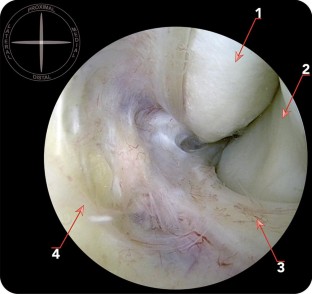

Connections were found in all cases between the ATFL and PTFL, the ATFL and CFL, and the CFL and PTFL. Connections between ATFL and PTFL were not homogeneous. Although connections between the ATFLif and PTFL were noted in all cases (40), only 17 ankles (42.5%) had connections between the ATFLsf and PTFL. The amount of fibres of connection was also variable.

Connections between the three components of the lateral collateral ligament of the ankle may be observed from the medial aspect of the ankle, and this may have important implications for arthroscopic lateral ligament repair.